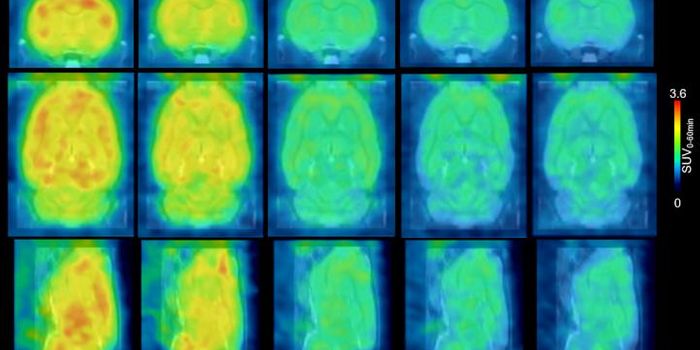

APR 03, 2018Clinical & Molecular DXScientists are improving the way PET scans work to detect diseases as early as possible with a new imaging agent. Focusi ...